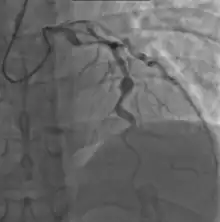

- Angiography was historically used to detect coronary artery aneurysms, and remains the gold standard for their detection, but is rarely used today unless coronary artery aneurysms have already been detected by echocardiography.

Heart complications are the most important aspect of Kawasaki disease, which is the leading cause of heart disease acquired in childhood in the United States and Japan.[31] In developed nations, it appears to have replaced acute rheumatic fever as the most common cause of acquired heart disease in children.[15] Coronary artery aneurysms occur as a sequela of the vasculitis in 20–25% of untreated children.[52] It is first detected at a mean of 10 days of illness and the peak frequency of coronary artery dilation or aneurysms occurs within four weeks of onset.[48] Aneurysms are classified into small (internal diameter of vessel wall <5 mm), medium (diameter ranging from 5–8 mm), and giant (diameter > 8 mm).[31] Saccular and fusiform aneurysms usually develop between 18 and 25 days after the onset of illness.[15]

Many risk factors predicting coronary artery aneurysms have been identified,[21] including persistent fever after IVIG therapy,[56][57] low hemoglobin concentrations, low albumin concentrations, high white-blood-cell count, high band count, high CRP concentrations, male sex, and age less than one year.[58] Coronary artery lesions resulting from Kawasaki disease change dynamically with time.[3] Resolution one to two years after the onset of the disease has been observed in half of vessels with coronary aneurysms.[59][60] Narrowing of the coronary artery, which occurs as a result of the healing process of the vessel wall, often leads to significant obstruction of the blood vessel and the heart not receiving enough blood and oxygen.[59] This can eventually lead to heart muscle tissue death, i.e., myocardial infarction (MI).[59]